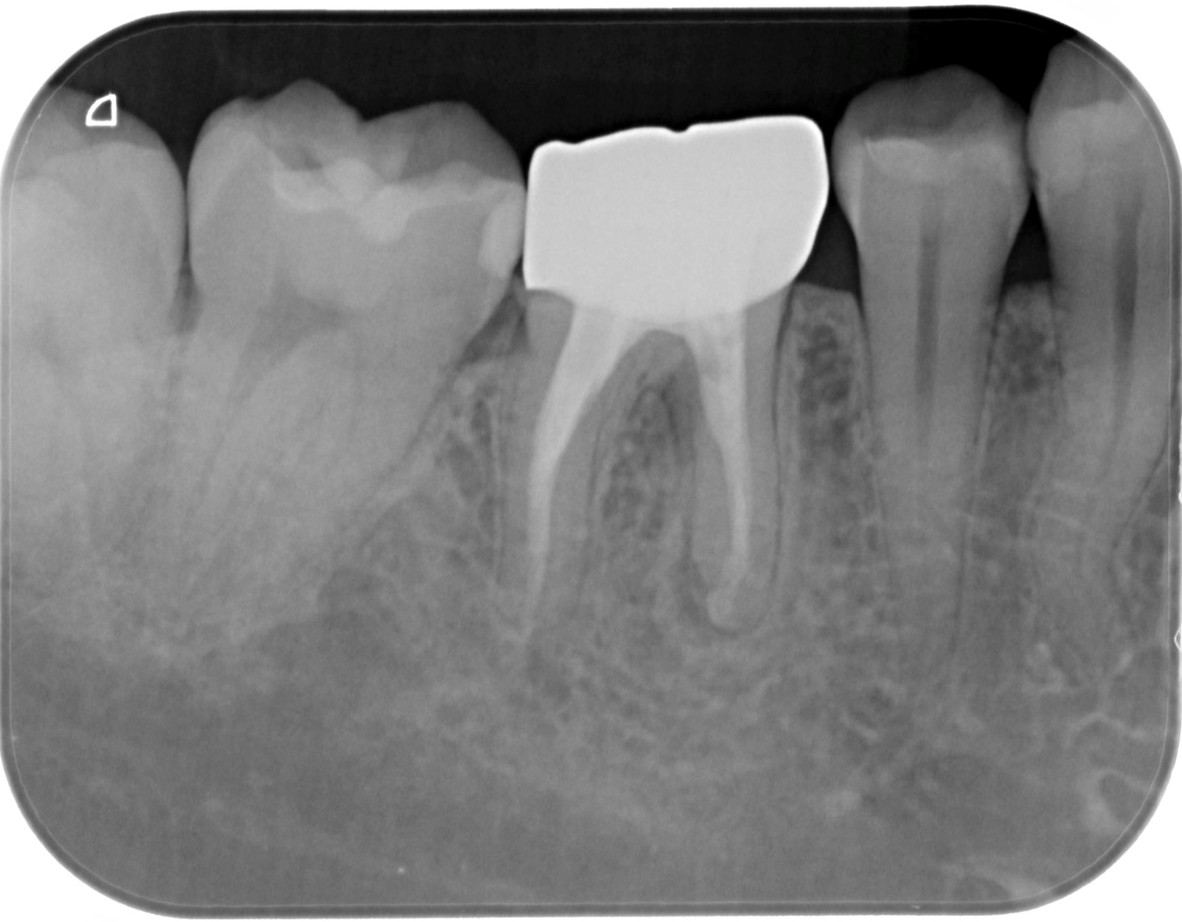

症例4

| 項目 | 詳細 |

|---|---|

| 患者様データ | 60代 女性 |

| 来院時の主訴 | 「残りの人生を健康的に噛めるようになりたい。」 |

| 医院の診断 |

虫歯の再発、歯周病を併発した慢性根尖性歯周炎 |

| 通院期間 | 1年間 |

| 来院回数 | 8回 |

| 治療費 | 480,000円(税抜) 《内訳》 精密感染根管治療100,000円、ファイバーポストコア20,000円、セラミック治療120,000円×3 |

| リスクと副作用 | ①根管治療歯は長期的には破折するリスク ②メインテナンスが必要 |

| ココがこだわりのポイント☝ |

ラバーダム防湿とマイクロスコープを使用して丁寧に治療を行いました。 再根管治療のため、殺菌性があり歯を補強することのできる根管充填材料を使用しています。 歯周病を併発していましたが、患者様の日々の歯磨きの努力により、改善することができました。 |